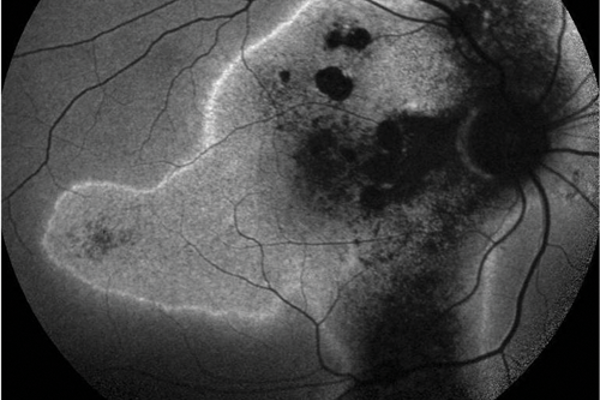

The management of chronic central serous chorioretinopathy

Marten E Brelen